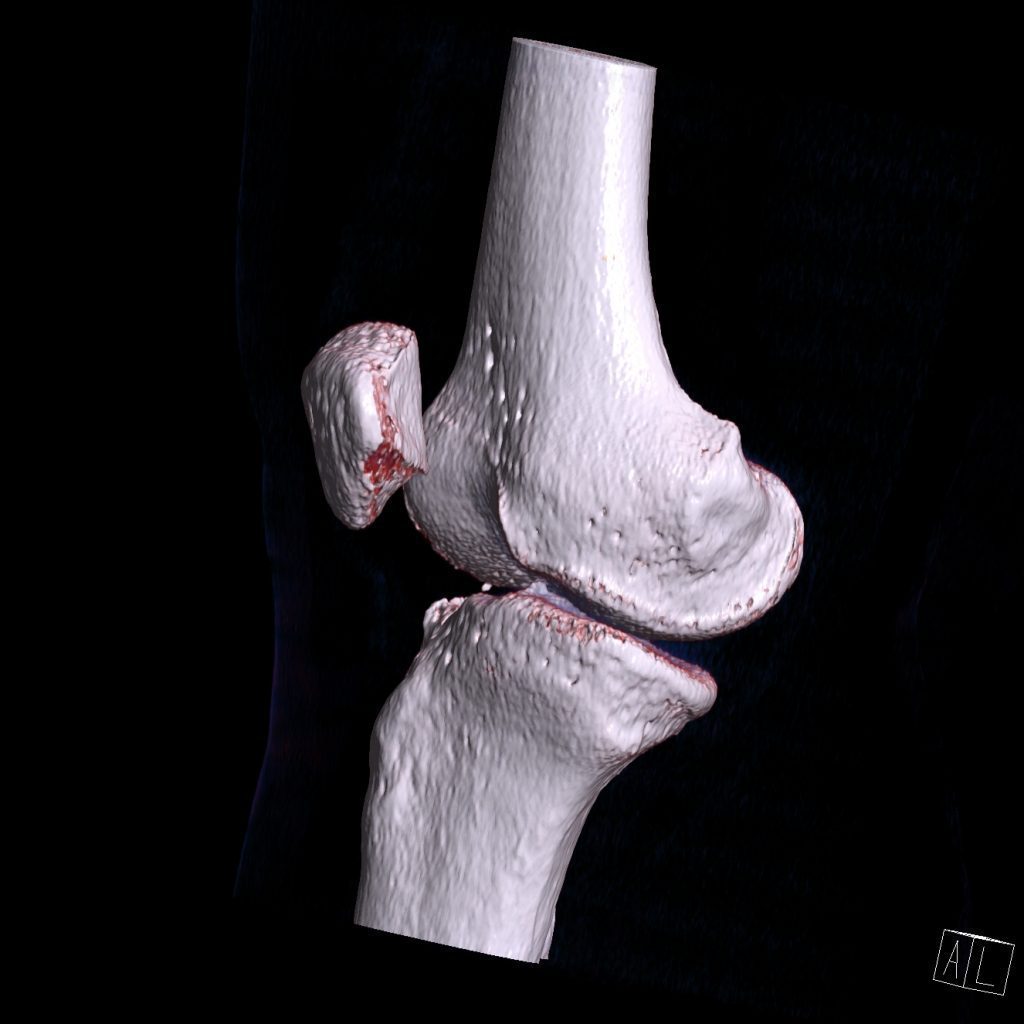

سي تي اسکن اسپيرال زانوي راست ( مولتي ديدکتور 16 با مقاطع ظريف و بازسازي هاي ساژيتال و کرونال و 3D):

– دفورميتي پلاتوي لترال تيبيا ناشي از depressed Fx و فرورفتگي در سطح مفصلي پلاتوي لترال

– نشانه هاي cortical Fx بدون جابجايي در کنديل لترال فمور

– loose body استخواني به ابعاد mm 2 x 3 در انترولترال مفصل زانو و

– افيوژن خفيف در مفصل زانو همراه با تورم نسج نرمي در اطراف آن

مشهود است .